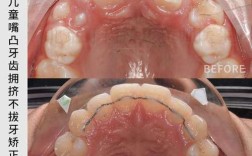

前磨牙区拔牙:最常见,兼顾功能与美观

前磨牙区(上下颌第一、第二前磨牙)是正畸拔牙的“主力区域”,因位置居中、牙根较短(单根或双根,且分叉小)、拔除后对咀嚼功能影响相对较小,且能为前牙内收和后牙调整提供充足空间,成为大多数拔牙方案的首选。